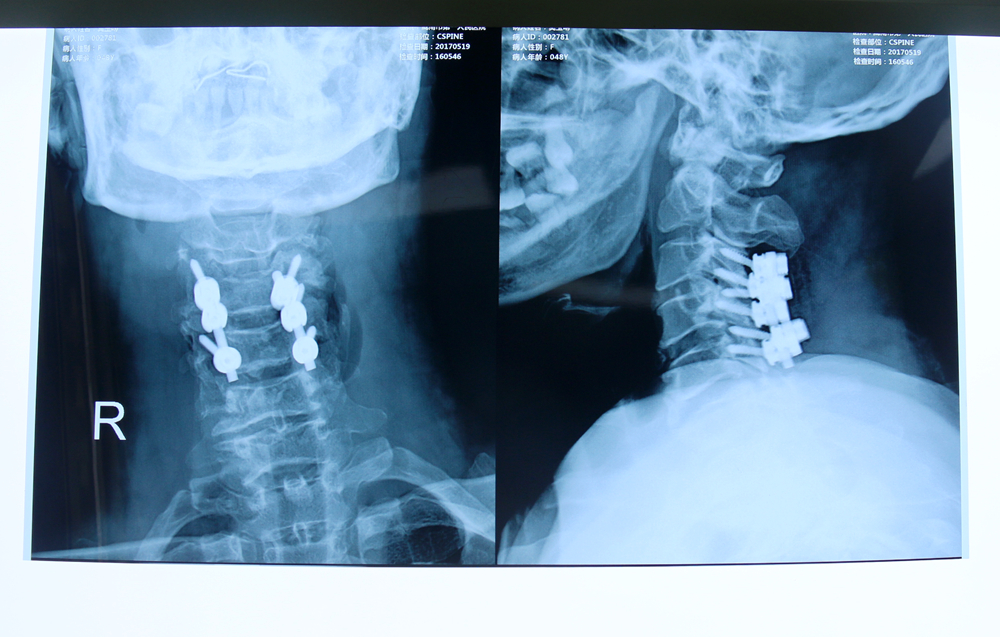

术后影像资料

患者,女,48岁,渐进性四肢肌力、感觉减退伴行走不便2月余。入院后行颈椎磁共振:颈3-4、4-5、6-7椎间盘突出,颈3-4、4-5椎间盘平面椎管狭窄,黄韧带肥厚。科主任协同主治大夫等人会诊后确定了手术方案,5月13日,在麻醉科的配合下,在全麻下行高位颈椎椎间盘突出并椎管狭窄后路减压侧块螺钉钉棒系统内固定术,术程顺利,患者术后恢复良好,现已佩戴护具下床。